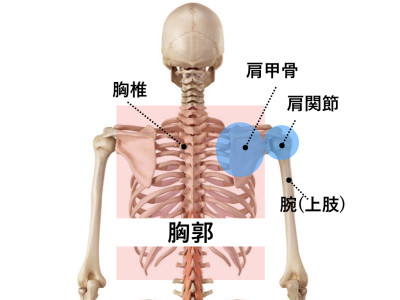

当院にお越しの男性のお客様。 「以前筋トレで上半身を鍛えていた」 「仕事で荷物をよくもつ」 「最近筋トレで上半身を鍛えている」 など比較的上半身の筋肉がしっかりとついている方々が首の痛みを訴えるケースが結構あります。 そして皆さんに共通しているのがそれら上半身の筋肉の柔軟性がないという事。 柔軟性がない事により【胸郭(きょうかく)】の動きが皆さん悪い。(※胸郭⇒下の画像を参考に) 全ての関節がしっかりと動いていればどこかの関節に負担がかかる事はないのですが、動きが悪いところがあれば他の関節でその動きを補わなければなりません。 体を捻る・反るなどの動きの際は胸郭の動きが重要です。(首を左右にひねる・頭を後ろに倒すなど) 首の下にある胸郭の動きが悪ければ首がその動きを補わなければいけません。 結果的に動きを補った部分は、通常の倍の負担がかかるわけですから痛みもでてきやすいというわけです。 比較的上半身の筋肉量がある方は、しっかりとストレッチを取り入れて、胸郭の動きが悪くならないように気を付けて下さい!! 首・腰・ひざなどの関節の痛みは【関節の痛み専門院】トータルボディサポートEBMまでお気軽にご相談ください。 トータルボディサポート EBM 住所 〒862-0971 熊本県熊本市中央区大江6-21-8白井ビル1F TEL 096-366-9555 当院Facebookはこちら http://on.fb.me/1StrBpJ